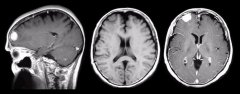

嗅沟脑膜瘤MRI怎么看?手术后会复发吗?MRI(磁共振成像)是诊断嗅沟脑膜瘤的重要影像学工具,其能够提供高对比度、高分辨率的脑部图像,对于肿瘤的位置、...

从MRI和CT影像上来看,肿瘤的控制成功,没有肿瘤残余,也并无手术并发症的产生。建议2-3年再次复查MRI。这是INC国际神经外科顾问团的德国Helmut Bertalanf...